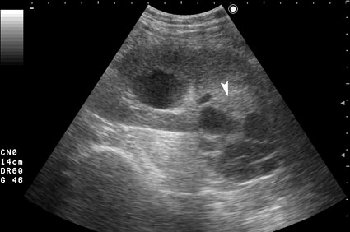

Серошкальное УЗИ. В области нижнего полюса определяется образование сложной структуры (стрелка).